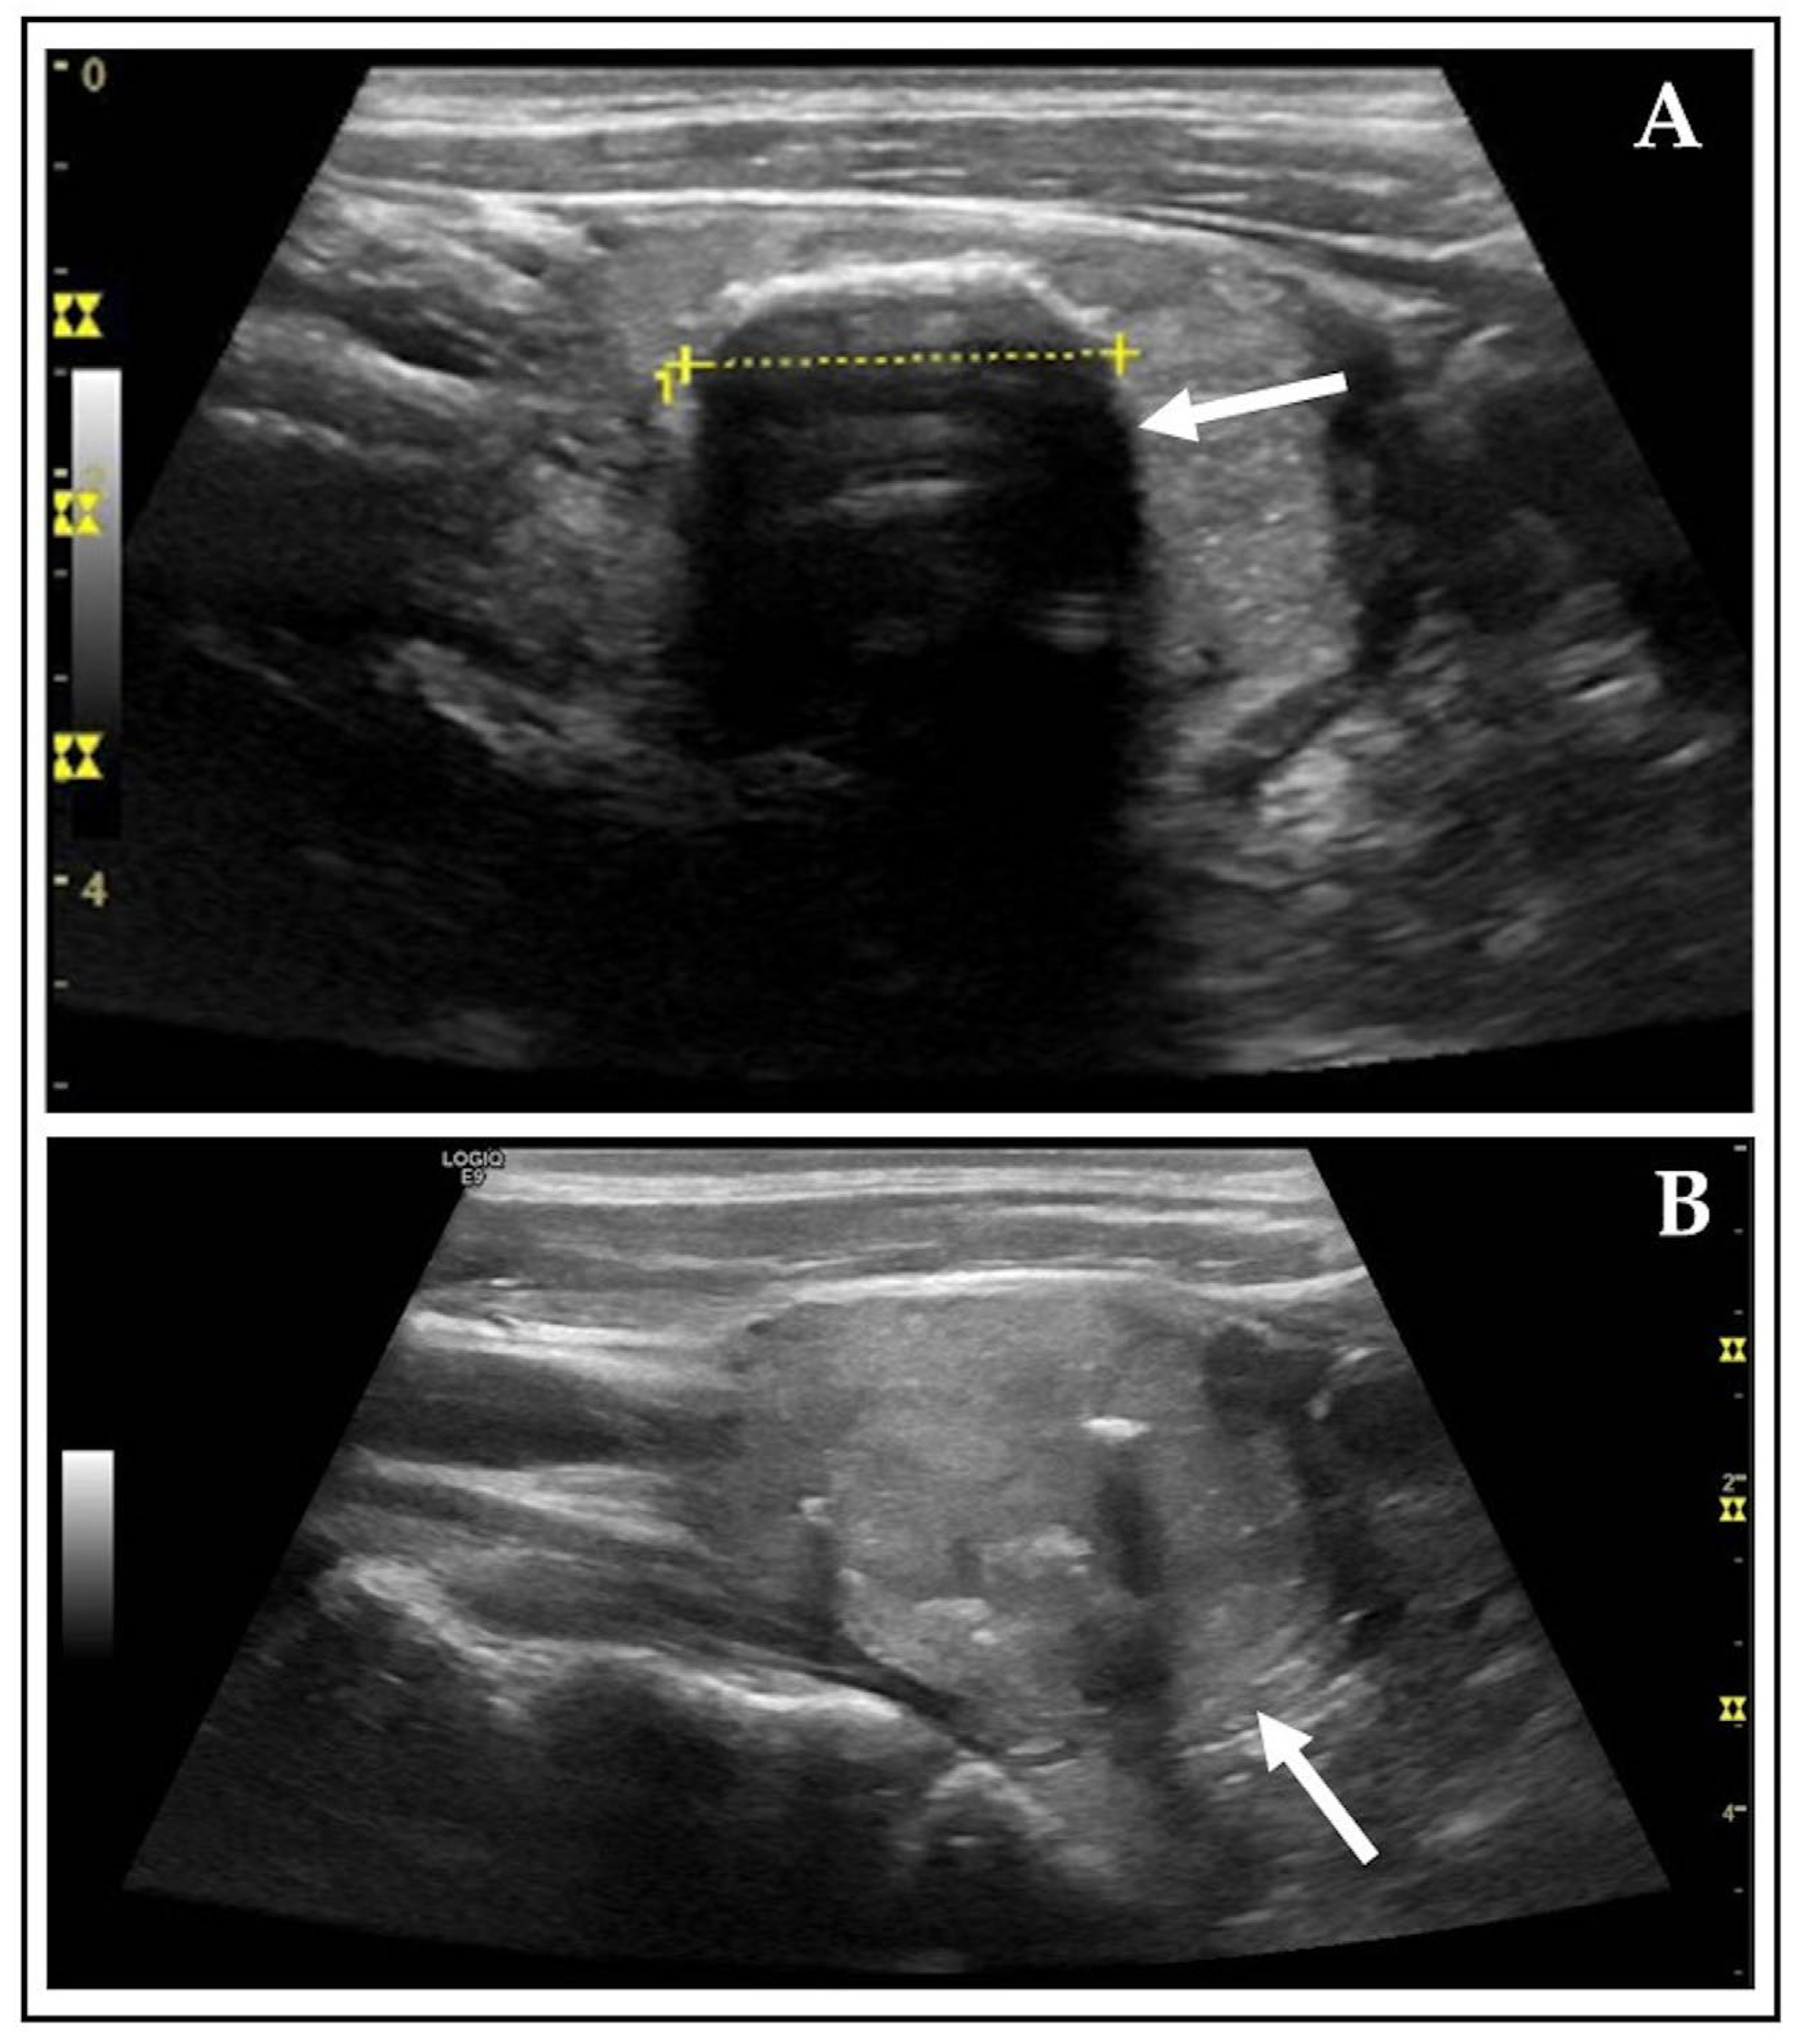

| AFTNs incompletely displayed | 3 (0.7) | 2 (0.5) | p = 0.999 |

| AFTNs incompletely displayed | 73 (17.2) | 5 (1.2) | p < 0.001 |

| Isthmus | 12 (2.8) | 1 (0.2) | p = 0.003 |

| Upper pole | 3 (0.7) | 0 (0.0) | p = 0.249 |

| Lower pole | 39 (9.2) | 3 (0.7) | p < 0.001 |

| Central | 19 (4.5) | 1 (0.2) | p < 0.001 |